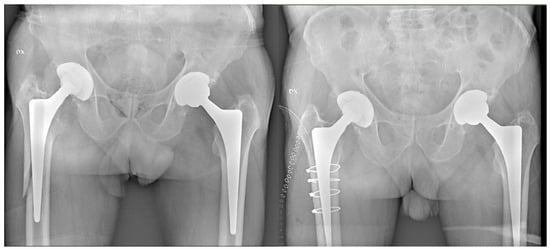

Periprosthetic Hip Fractures around the Stem: Can the Stem Design Affect Fracture Features?

2. Material and Methods

3. Results